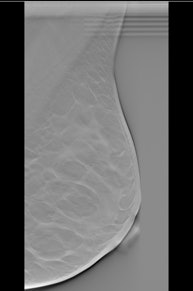

Left: Example of a breast tomosynthesis slice holding a simulated mass. Right: Example of a breast tomosynthesis slice holding a simulated microcalcification cluster. All images courtesy of Dr. Pontus Timberg.Image volumes can be viewed using free scroll volume browsing (FS) or in a cine loop. The standard procedure is FS, but in clinical practice observers often use a cine loop to get an overview of the images. In addition, breast tomosynthesis images may be displayed on the monitor in either vertical or horizontal orientation. The researchers evaluated the efficiency of several breast tomosynthesis image volume readings using an experimental setup. They assessed these in terms of lesion detection performance, time efficiency, visual attention, and search using jack-knife alternative free-response receiver operating characteristics (JAFROC) and eye tracking.

The researchers selected 55 normal breast tomosynthesis cases in mediolateral oblique view, which were then verified by an expert radiologist panel. The exams were acquired with a Siemens Mammomat Novation BT prototype (Siemens Healthcare). All viewing procedures consisted of FS, and three were combined with initial cine loops at three different frame rates (9, 14, and 25 fps). The presentation modes consisted of vertically and horizontally orientated image volumes.